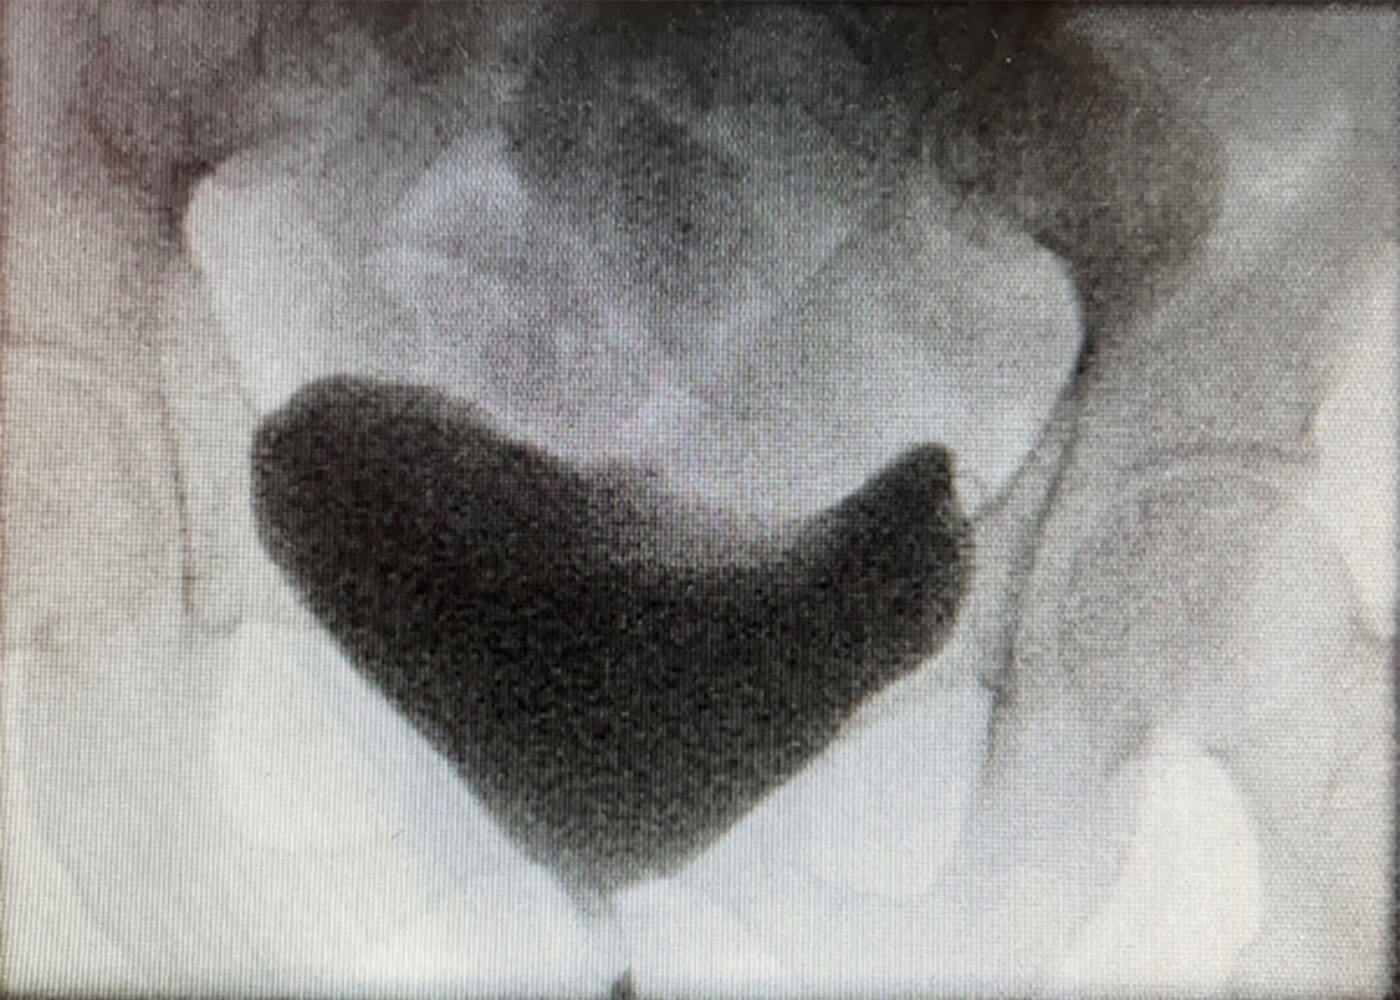

Figure 1a.

- Figure 1a is a video-urodynamic image taken when the patient was asked to cough. It demonstrates leakage of urine on coughing. Figure 1b is a urodynamics trace which shows leakage of urine (pink line) when the abdominal pressure (red line) is raised on coughing while the detrusor pressure (green line) is not raised.